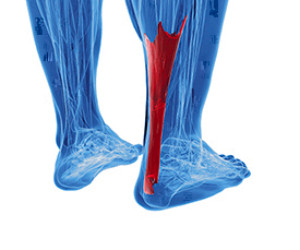

Types of Achilles Tendon Injuries

Tendons are bands of tissue that connect muscles and bones together. The Achilles tendon is located on the back of the ankle and connects the calf muscles to the heel. Tendonitis occurs when the tendon becomes inflamed. Tendinosis occurs when the tendon degenerates, usually due to overuse. Paratenonitis is a result of tissue around the tendon becoming inflamed and thickened, eventually attaching to the tendon. Insertional Achilles tendinopathy happens when the fibers attaching to the heel bone inflame and eventually degenerate. Another serious injury that can happen is an Achilles tendon rupture, which will make walking and standing extremely difficult and will likely require surgery. Because of the seriousness of Achilles tendon injuries, seeing a podiatrist for diagnosis and treatment is very important.

Tendons are bands of tissue that connect muscles and bones together. The Achilles tendon is located on the back of the ankle and connects the calf muscles to the heel. Tendonitis occurs when the tendon becomes inflamed. Tendinosis occurs when the tendon degenerates, usually due to overuse. Paratenonitis is a result of tissue around the tendon becoming inflamed and thickened, eventually attaching to the tendon. Insertional Achilles tendinopathy happens when the fibers attaching to the heel bone inflame and eventually degenerate. Another serious injury that can happen is an Achilles tendon rupture, which will make walking and standing extremely difficult and will likely require surgery. Because of the seriousness of Achilles tendon injuries, seeing a podiatrist for diagnosis and treatment is very important.

Achilles tendon injuries need immediate attention to avoid future complications. If you have any concerns, contact one of our podiatrists of PA Foot & Ankle Associates. Our doctors can provide the care you need to keep you pain-free and on your feet.

What Is the Achilles Tendon?

The Achilles tendon is a tendon that connects the lower leg muscles and calf to the heel of the foot. It is the strongest tendon in the human body and is essential for making movement possible. Because this tendon is such an integral part of the body, any injuries to it can create immense difficulties and should immediately be presented to a doctor.

What Are the Symptoms of an Achilles Tendon Injury?

There are various types of injuries that can affect the Achilles tendon. The two most common injuries are Achilles tendinitis and ruptures of the tendon.

Achilles Tendinitis Symptoms

- Inflammation

- Dull to severe pain

- Increased blood flow to the tendon

- Thickening of the tendon

Rupture Symptoms

- Extreme pain and swelling in the foot

- Total immobility

Treatment and Prevention

Achilles tendon injuries are diagnosed by a thorough physical evaluation, which can include an MRI. Treatment involves rest, physical therapy, and in some cases, surgery. However, various preventative measures can be taken to avoid these injuries, such as:

- Thorough stretching of the tendon before and after exercise

- Strengthening exercises like calf raises, squats, leg curls, leg extensions, leg raises, lunges, and leg presses

Achilles Tendon Injuries

The Achilles tendon is the largest tendon in the body; it is a tough band of fibrous tissue that stretches from the bones of the heel to the calf muscles. This tendon is what allows us to stand on our toes while running, walking, or jumping, it is common for this tendon to become injured. In severe cases, the Achilles tendon may become partially torn or completely ruptured. However, this tendon is susceptible to injury because of its limited blood supply and the high level of tension it endures.

The people who are more likely to suffer from Achilles tendon injuries are athletes who partake in activities that require them to speed up, slow down, or pivot. Consequently, athletes who engage in running, gymnastics, dance, football, baseball, basketball, or tennis are more likely to suffer from Achilles tendon injuries. Additionally, there are other factors that may make you more prone to this injury. People who wear high heels, have flat feet, tight leg muscles or tendons, or take medicines called glucocorticoids are more likely to have Achilles tendon injuries.

A common symptom of an Achilles tendon injury is pain above the heel that is felt when you stand on your toes. However, if the tendon is ruptured, the pain will be severe, and the area may become swollen and stiff. Other symptoms may be reduced strength in the lower ankle or leg area, and reduced range of motion in the ankle. When the Achilles tendon tears, there is usually a popping sound that occurs along with it. People who have acute tears or ruptures may find walking and standing to be difficult.

If you suspect you have injured your Achilles tendon, you should see your podiatrist to have a physical examination. Your podiatrist will likely conduct a series of tests to diagnose your injury including a “calf-squeeze” test. Calf squeeze tests are performed by first squeezing the calf muscle on the healthy leg. This will pull on the tendon and consequently cause the foot to move. Afterward, the same test will be performed on the injured leg. If the tendon is torn, the foot won’t move because the calf muscle won’t be connected to the foot.